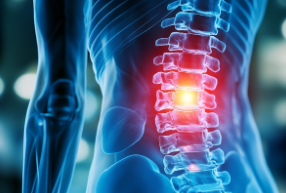

2. 허리 통증이 있을 때 무조건 쉬는 것이 맞는가

외상 직후의 급성 통증은 안정을 요하지만, 일반적인 허리 통증 관리의 원칙은 오히려 ‘움직임 유지’입니다. 장시간 누워 있으면 근육 강도가 빠르게 감소하고, 척추 주변 근육이 약해져 통증이 악화될 수 있습니다. 허리 통증 환자에게 가벼운 걷기, 스트레칭, 코어 근력운동을 권하는 이유가 여기에 있습니다. 과도한 격한 운동은 현실적으로 어렵지만, 가능한 범위에서 규칙적으로 움직이면 통증 회복 속도가 올라갑니다. 통증 관리에서 ‘적절한 활동 유지’는 매우 중요한 의학적 기전입니다.